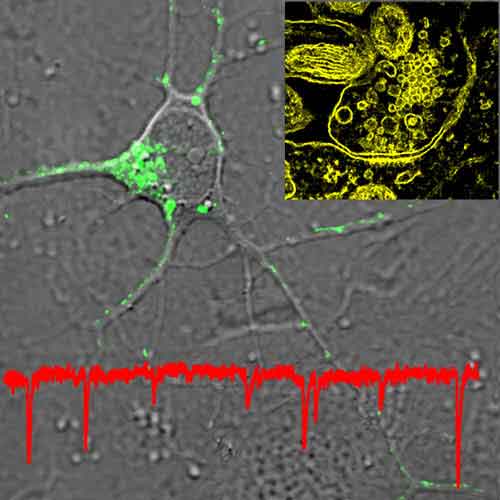

In quest’ultima ricerca, infatti è stata utilizzata la tecnica di imagingdenominata tomografia a schiera (array tomography) e inventata da Stephen Smith, professore di fisiologia molecolare e cellulare della Stanford e dalla sua collaboratrice Kristina Micheva, per ottenere sezioni di corteccia cerebrale di soli 70 nanometri di spessore ciascuna.

I campini di corteccia utilizzati provenivano da topi geneticamente ingegnerizzati inserendo un gene che codifica per la proteina fluorescente verde, prelevato da una specie di medusa.

Le sezioni sono poi state colorate mediante anticorpi in grado di legarsi selettivamente a 17 differenti proteine associate alle sinapsi e ulteriormente modificate mediante coniugazione a molecole che rispondono alla luce in differenti modi, differenziandosi ulteriormente rispetto ai neuroni fluorescenti.

Ciascuna sinapsi ha così acquisito una propria “firma” dovuta alla particolare composizione proteica che ha permesso la compilazione di un catalogo estremamente accurato dei diversi tipi di sinapsi.

Secondo quanto riferito sulla rivista Neuron, tutte le informazioni ottenute con le foto, inoltre, sono state memorizzate ed elaborate grazie a un nuovo software per ottenere, infine, immagini tridimensionali che possono essere ruotate, penetrate e analizzate dai ricercatori.